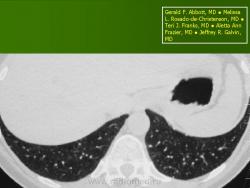

Изменения в позвоночнике наблюдались только в 2-х случаях. Тела позвонков при этом были сплющены до узкой пластинки, имели уплотненную структуру (Рис. 3).

Полисистемный вариант ГКЛ установлен 7 детям в возрасте от 9 мес. до 2-х лет. Болезнь дебютировала астеническим синдромом (вялостью, слабостью, беспокойством, снижением аппетита), длительной фебрильной лихорадкой у 4-х детей, увеличением лимфатических узлов в виде конгломератов у 2-х. Поражение кожи наблюдалось у 3-х пациентов в виде геморрагической петехиальной сыпи, себорейного дерматита волосистой части головы и изъявления естественных складок. Гепатоспленомегалия отмечалась у 3-х (значительно увеличивались размеры селезенки - нижний край определялся в малом тазу), у одного ребенка развился синдром несахарного диабета. В анализах периферической крови в 4-х случаях выявлялся выраженный нейтрофильный лейкоцитоз до 30 тыс/мкл со сдвигом влево, тяжелая анемия, требовавшая заместительной терапии, тромбоцитопения, ускорение СОЭ до 30мм/час. В тяжелом состоянии госпитализировано 6 больных. Диагноз мультисистемный ГКЛ установлен на основании гистологического исследования пораженной ткани (кожи, лимфоузла, кости, селезенки), КТ, МРТ, миелограммы. Хирургическое лечение, спленэктомия, поведено 1 ребенку, в катамнезе без осложнений и рецидива заболевания. Химиотерапию получили 5 детей: протокол DAL-HX-83 (2), протокол LCHII(3). В РДКБ (г.Москва) направлен 1 ребенок с полисистемным ГКЛ: поражение кожи, лимфоузлов, печени, селезенки, легких, костного мозга, множественные костные деструкции; положительный эффект достигнут после блоков химиотерапии с применением кладрибина, цитозара, солу-медрола; в настоящее время на поддерживающей терапии. В катамнезе у 6 детей с полисистемным ГКЛ отмечены осложнения: несахарный диабет (3), компрессионный перелом позвоночника (2) (рис. 4), неполная клиническая ремиссия (2).

Рис. 4.Больной Б.С., 14 лет. МРТ позвоночного столба. Компрессионный перелом тел Th2, Th5, Th6, Th8, Th12 позвонков Iстепени на фоне ГКЛ.